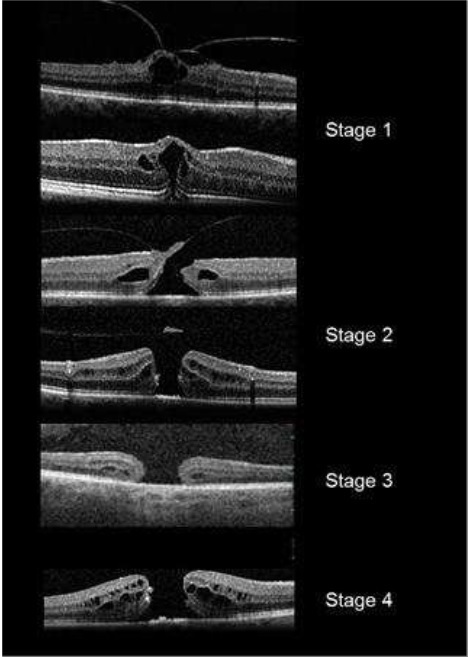

Qual é a classificação do Buraco de Macula?

Classificação de Gass

Estágio 1: Buraco macular iminente

- 1a: Pseudocisto foveal

- 1b: Descontinuidade da retina externa (até 300 micrômetros)

Estágio 2: BM<400 micrômetros + Hialóide aderida à fóvea

Estágio 3: BM > 400 micrômetros + Hialóide solta da fóvea mas permanece aderida ao disco

Estágio 4: BM + DVP completo